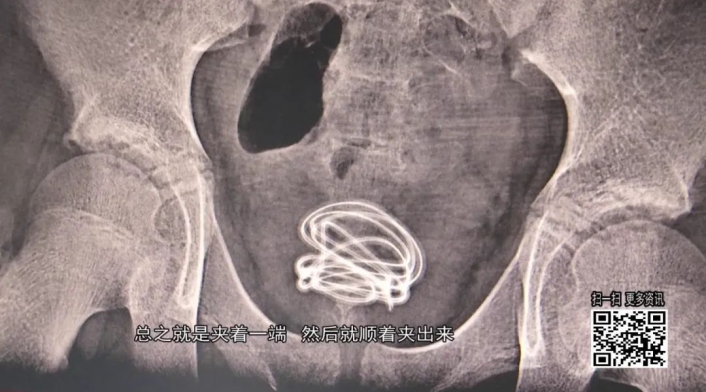

Medios como Global Times informaron que el cable eléctrico terminó enredado en la vejiga del pre-adolescente quien guardó silencio durante más de tres meses.

Al no soportar el dolor el niño fue trasladado al hospital donde fue sometido a una cirugía de urgencia en la que los expertos lograron extraer 70 centímetros de cable.

Según declaraciones del médico a cargo de la cirugía, el cable originalmente era negro; sin embargo, debido al tiempo dentro del cuerpo y al estar cubierto de orina y otros líquidos, salió con un color gris.